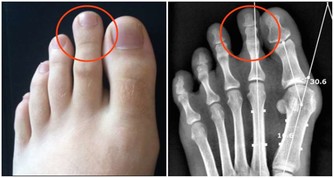

腎小球腎炎、糖尿病腎病、高血壓腎病、痛風腎、多囊腎等都被統稱為“慢性腎病”。當腎臟受損時,患者體內的毒素難以被過濾,逐漸會引起上述症狀。而這類疾病通常無法根治,唯有找到致病原因、確定疾病類型,才能通過相應的治療控制病情,緩解不適感。常見的檢查方法包括血液檢查、放射性核素腎掃描、活體組織檢查等。